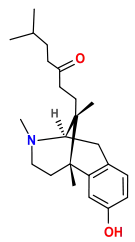

Benzomorphans

- 5,9 alpha-diethyl-2-hydroxybenzomorphan (5,9-DEHB)

- 8-Carboxamidocyclazocine (8-CAC)

- Alazocine

- Anazocine

- Bremazocine

- Butinazocine

- Carbazocine

- Cogazocine

- Cyclazocine

- Dezocine

- Eptazocine

- Etazocine

- Ethylketazocine

- Fedotozine

- Fluorophen

- Gemazocine

- Ibazocine

- Ketazocine

- Metazocine

- Moxazocine

- Pentazocine

- Phenazocine

- Quadazocine

- SKF-10047

Structures

| Benzomorphans | ||||

|---|---|---|---|---|

5,9 alpha-diethyl-2-hydroxybenzomorphan 5,9 alpha-diethyl-2-hydroxybenzomorphan (5,9-DEHB) |

8-Carboxamidocyclazocine 8-Carboxamidocyclazocine |

Alazocine Alazocine |

Anazocine Anazocine |

Bremazocine Bremazocine |

Butinazocine Butinazocine |

Carbazocine Carbazocine |

Cogazocine Cogazocine |

Cyclazocine Cyclazocine |

Dezocine Dezocine |

Eptazocine Eptazocine |

Etazocine Etazocine |

Ethylketocyclazocine Ethylketocyclazocine |

Fedotozine Fedotozine |

Fluorophen Fluorophen |

Gemazocine Gemazocine |

Ibazocine Ibazocine |

Ketazocine Ketazocine |

Metazocine Metazocine |

Moxazocine Moxazocine |

Pentazocine Pentazocine |

Phenazocine Phenazocine |

Quadazocine Quadazocine

|

Thiazocine Thiazocine |

Tonazocine Tonazocine |

Volazocine Volazocine |

Zenazocine Zenazocine |